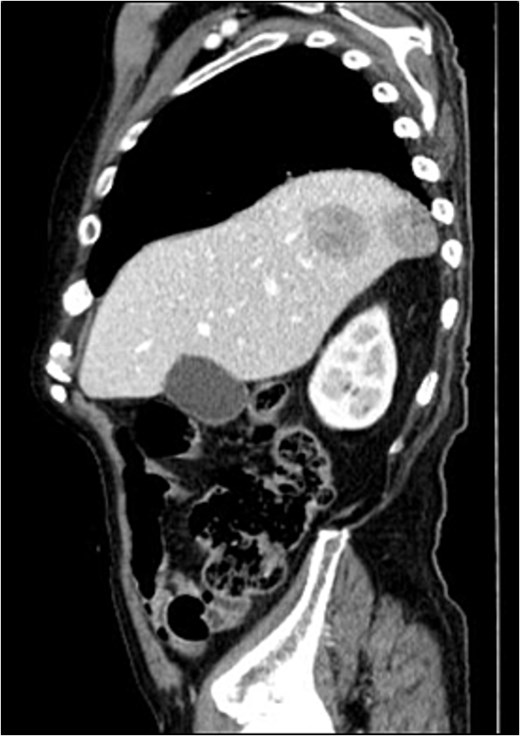

A contrast-enhanced chest-abdominal-pelvic computed tomography (CT) scan revealed a solid, multilobular mass, with approximately 8 × 6 × 8 cm, likely originating from the SB, with asymmetric wall thickening, heterogeneous contrast enhancement, areas consistent with necrosis and central calcification (Figs 1 and 2), suggestive of GIST. Simultaneously, a solid nodular lesion was identified on the anterior wall of the rectum, exhibiting exophytic growth with a heterogeneous texture, well-defined borders and measuring 5 × 3 cm, without adjacent fat infiltration, raising suspicion of another GIST (Fig. 3).